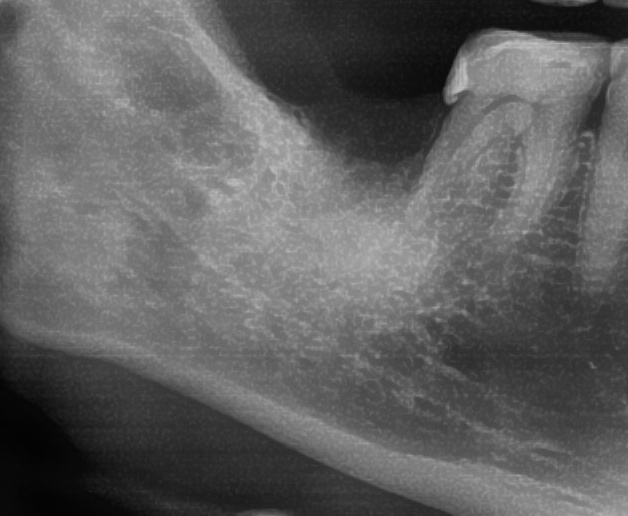

今回の患者様はインプラント植立を希望され、右下7番目の植立が決まりました。

しっかりとインプラント埋め込まれた後は、動揺がないか、噛んだ時に当たらないかなどを確認して、最後にパノラマ写真を撮影して今回のオペは終了となりました。